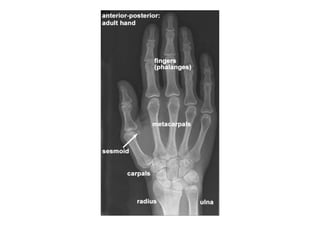

RADIOLOGIA DO

TRAUMA DO ESQUELETO

Referência: http://www.accessexcellence.org/RC/VL/

figura